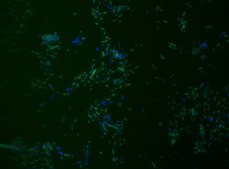

Fluorescent In Situ Hybridization technique (FISH) is based on the hybridization of fluorescent labeled oligonucleotide probe to a specific complementary DNA or RNA sequence in whole and intact cells.Microbial FISH allows the visualization, identification, and isolation of bacteria due to recognition of ribosomal RNA also in unculturable samples. FISH technique can serve as a powerful tool in the microbiome research field by allowing the observation of native microbial populations in diverse microbiome environments, such as samples from human origin (blood3 and tissue4), microbial ecology (solid biofilms5 and aquatic systems6) and plants7. It is strongly recommended to include positive and negative controls in FISH assays to ensure specific binding of the probe of interest and appropriate protocol conditions. We offer positive (MBD0032/33) and negative control (MBD0034/35) probes, that accompany the specific probe of interest. Akkermansia muciniphila probe specifically recognizes Akkermansia muciniphila cells. Akkermansia muciniphila is a gram negative, oval shaped, non-motile, non-spore forming strictly anaerobic bacteria.8 A. muciniphila inhabits the gastrointestinal tracts of more than 90% of adults and constitutes 1 to 4% of the fecal microbiota.9 It is one of the top 20 most abundant species detectable in the human gut.10 The mucus layer of the human intestine is a niche which is colonized by specific bacteria such as A. muciniphila. A. muciniphila can degrade mucin, a key mucus component, using the enzymes sialidase and fucosidase, and utilize it as a source of carbon and nitrogen.11 Consequently, the host produces additional mucus while the bacterium produces oligosaccharides and Short Chain Fatty Acids (SCFAs) that can be utilized by the host and trigger the immune system. An additional protective effect of the SCFA is stimulation of mucus-associated microbiota growth, that serves as a barrier against penetration of pathogens to intestinal cells.9,12 It was found that A. muciniphila abundance in the gut was correlated to a healthy intestine and inversely correlated to many disease conditions.11 In comparison to healthy controls, A. muciniphila levels were low in patients with intestinal disorders, such as inflammatory bowel disease (IBD), but also in other conditions, such as autism, atopy, and obesity.11,13-16 Therefore, the level of A. muciniphila was suggested to serve as a biomarker for healthy intestine.17 A. muciniphila is a promising potential probiotic that can be administrated for the treatment of diseases such as, colitis, metabolic syndromes, immune diseases, and cancer.10 FISH technique was successfully used to identify A. muciniphila with the probe in various samples such as pure culture (as described in the figure legends18), fecal samples19-21, gut lumen content22, appendix samples23, cecum content and tissue24,25 and colon tissue26. The probe can also be used for FISH coupled with flow cytometry (FCM-FISH)19,20,21, and FISH combined with Raman microspectroscopy

• Visualize, identify, and isolate Akkermansia muciniphila cells.

• Specific, sensitive, and robust identification of A. muciniphila in bacterial mixed population.

• Specific, sensitive, and robust identification even when A. muciniphila is in low abundance in the sample.

• Identify A. muciniphila in clinical samples such as, gut lumen content, appendix samples (formalin-fixed paraffin-embedded (FFPE) samples), fecal samples and colon tissue.